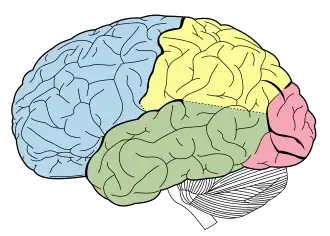

| Lobes of the human brain |

Advances in MRI technology have provided the ability to see the brain structure in great detail in an easy, non-invasive manner in vivo. Bartzokis et al., has noted that there is a decrease in grey matter volume between adulthood and old age, whereas white matter volume was found to increase from age 19–40, and decline after this age.[13] Studies using Voxel-based morphometry have identified areas such as the insula and superior parietal gyri as being especially vulnerable to age-related losses in grey matter of older adults.[13] Sowell et al., reported that the first 6 decades of an individual's life were correlated with the most rapid decreases in grey matter density, and this occurred over dorsal, frontal, and parietal lobes on both interhemispheric and lateral brain surfaces. It is also worth noting that areas such as the cingulate gyrus, and occipital cortex surrounding the calcarine sulcus appear exempt from this decrease in grey matter density over time.[13] Age effects on grey matter density in the posterior temporal cortex appear more predominantly in the left versus right hemisphere, and were confined to posterior language cortices. Certain language functions such as word retrieval and production were found to be located to more anterior language cortices, and deteriorate as a function of age. Sowell et al., also reported that these anterior language cortices were found to mature and decline earlier than the more posterior language cortices.[13] It has also been found that the width of sulcus not only increases with age,[14] but also with cognitive decline in the elderly.[15]